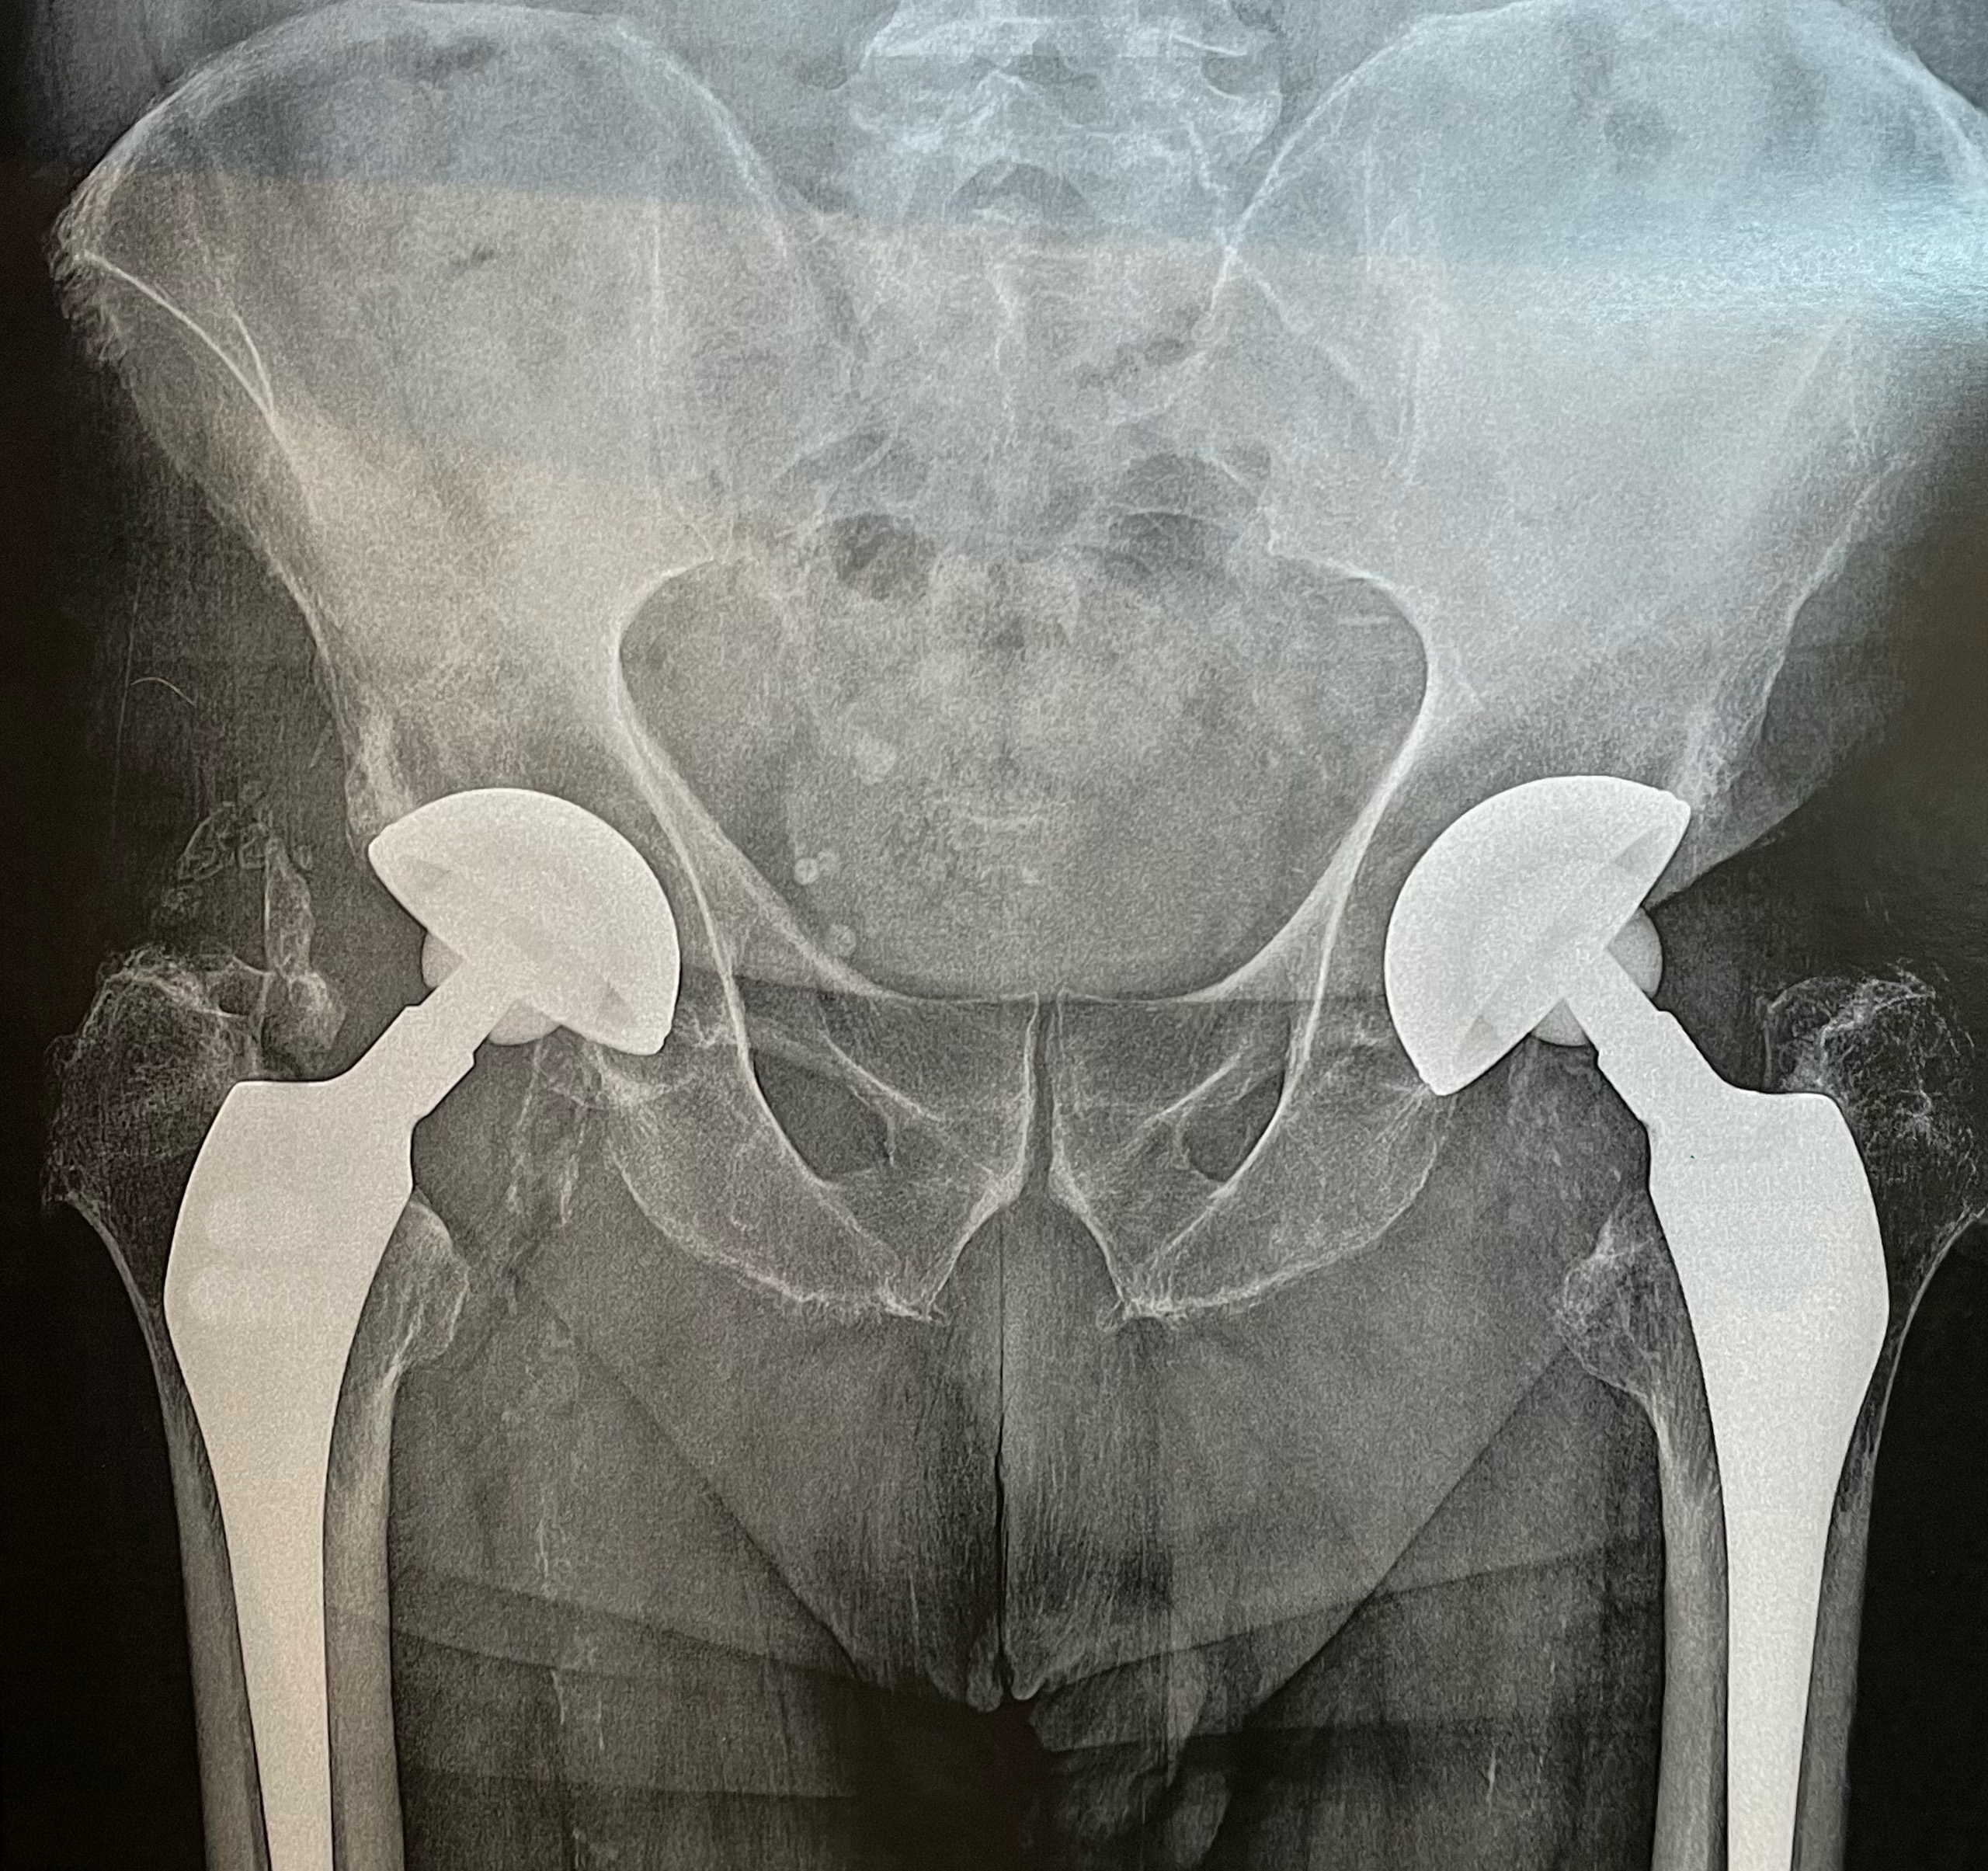

Spécialiste en chirurgie du genou et de la hanche.

Dr. Julien Synave est un chirurgien orthopédiste reconnu, spécialisé dans le traitement des pathologies complexes du genou, des articulations, ainsi que des membres inférieurs et supérieurs. Avec son expérience de plus de 30 ans, il vous proposera des solutions personnalisées pour soulager vos douleurs articulaires et améliorer votre mobilité.